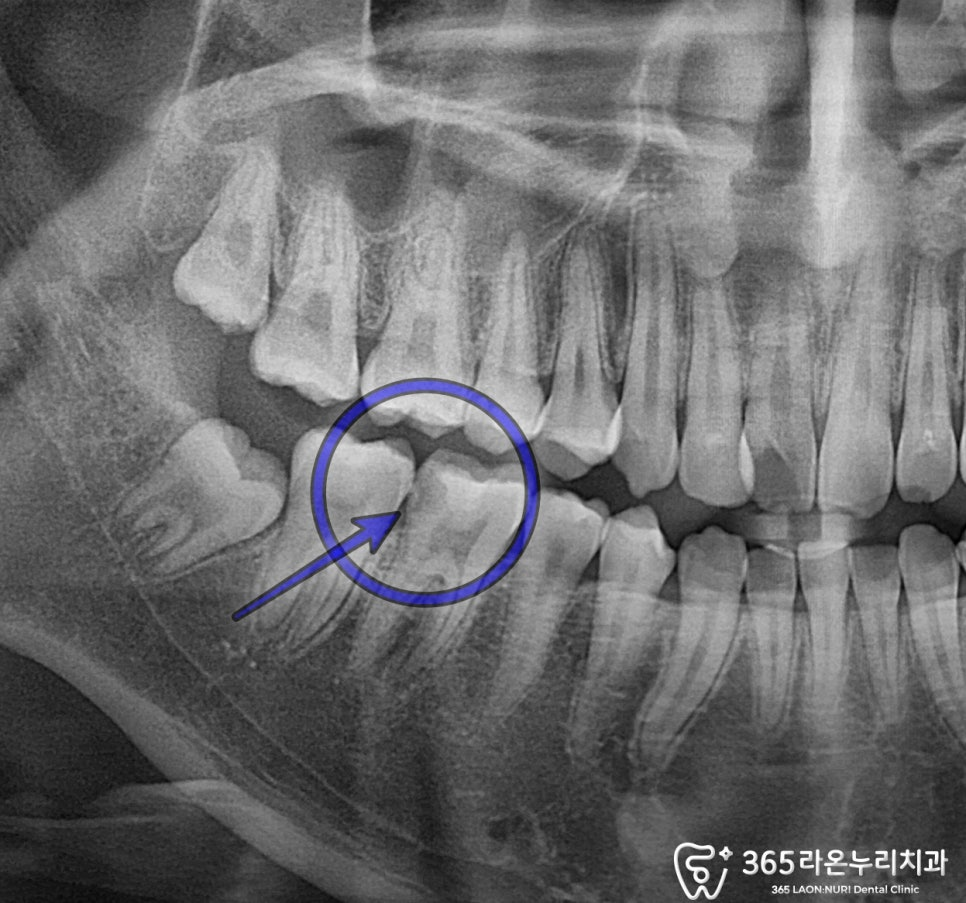

우선 오산대역 치과 에서

x-ray 사진을 보도록 하겠습니다.

인접면 충치가 엑스레이에서도

크게 보이고,

문제가 있는 곳을

자세히 확인해 보면

우식증으로 인해

하방으로2차 우식이 생겨

내부 조직이 충치균에 감염되었고,

이로 인한 통증이 나타나보입니다.